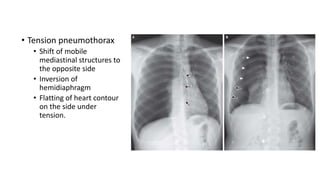

• Tension pneumothorax

• Shift of mobile

mediastinal structures to

the opposite side

• Inversion of

hemidiaphragm

• Flatting of heart contour

on the side under

tension.